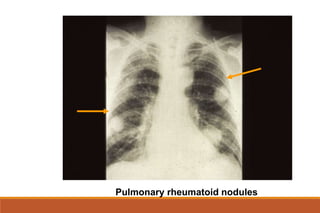

EXTRA-ARTICULAR MANIFESTATIONS

General: fever, lymphadenopaty,weit loss, fatigue

Dermatologic: rheumatoid nodules, vasculitis

Ocular manifestations: Keratoconjunctivitis sicca, episcleritis, scleritis, choroid and retinal nodules

Pulmonary manifestations: pleural involvement, fibrosing alveolitis , obliterative bronchiolitis

Pulmonary rheumatoid nodules